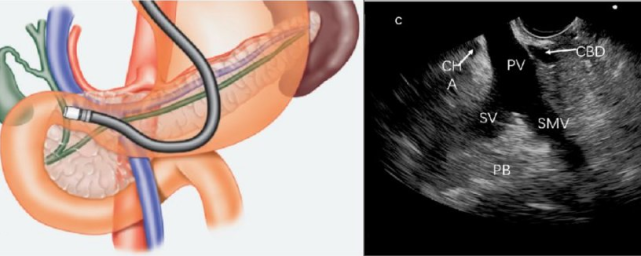

超声内镜与胆胰疾病

超声内镜有较高的敏感性,诊断胆胰疾病的准确率>95%,相比于CT、MRI、MRCP有独特优势,特别适合小病变的发现,如胰腺、壶腹部<1cm、胆总管<0.5mm的病变。

超声内镜由于紧贴病变部位,在对胆总管、壶腹部小占位病变性质的了解、肿瘤浸润深度的判断、病变与周围脏器的关系等方面表现出不可替代的优越性。

近年来,超声内镜已成为发现胆胰疾病患者首选的诊断方法。同时,超声内镜还能引导深层次组织脏器的穿刺活检,甚至通过穿刺、引流、注射及粒子种植等方法对胆胰疾病进行治疗。

胰腺疾病的诊断

超声内镜扫查胰腺实质,可以发现B超和CT无法发现的微小病变,还可以对病灶部位进行超声内镜引导下细针穿刺活检(EUS-FNA)。除了肿瘤本身,对周围淋巴结、器官的扫描可以辅助疾病分期。

肝脏、胆管及十二指肠壶腹部病变的诊断

对于存在梗阻性黄疸的患者,沿胆管走行扫查可以精确定位梗阻位置,通过观察梗阻部位病变的形态及回声特点,判断病因是结石、肿瘤或者其他疾病,并明确周围组织器官受累情况。